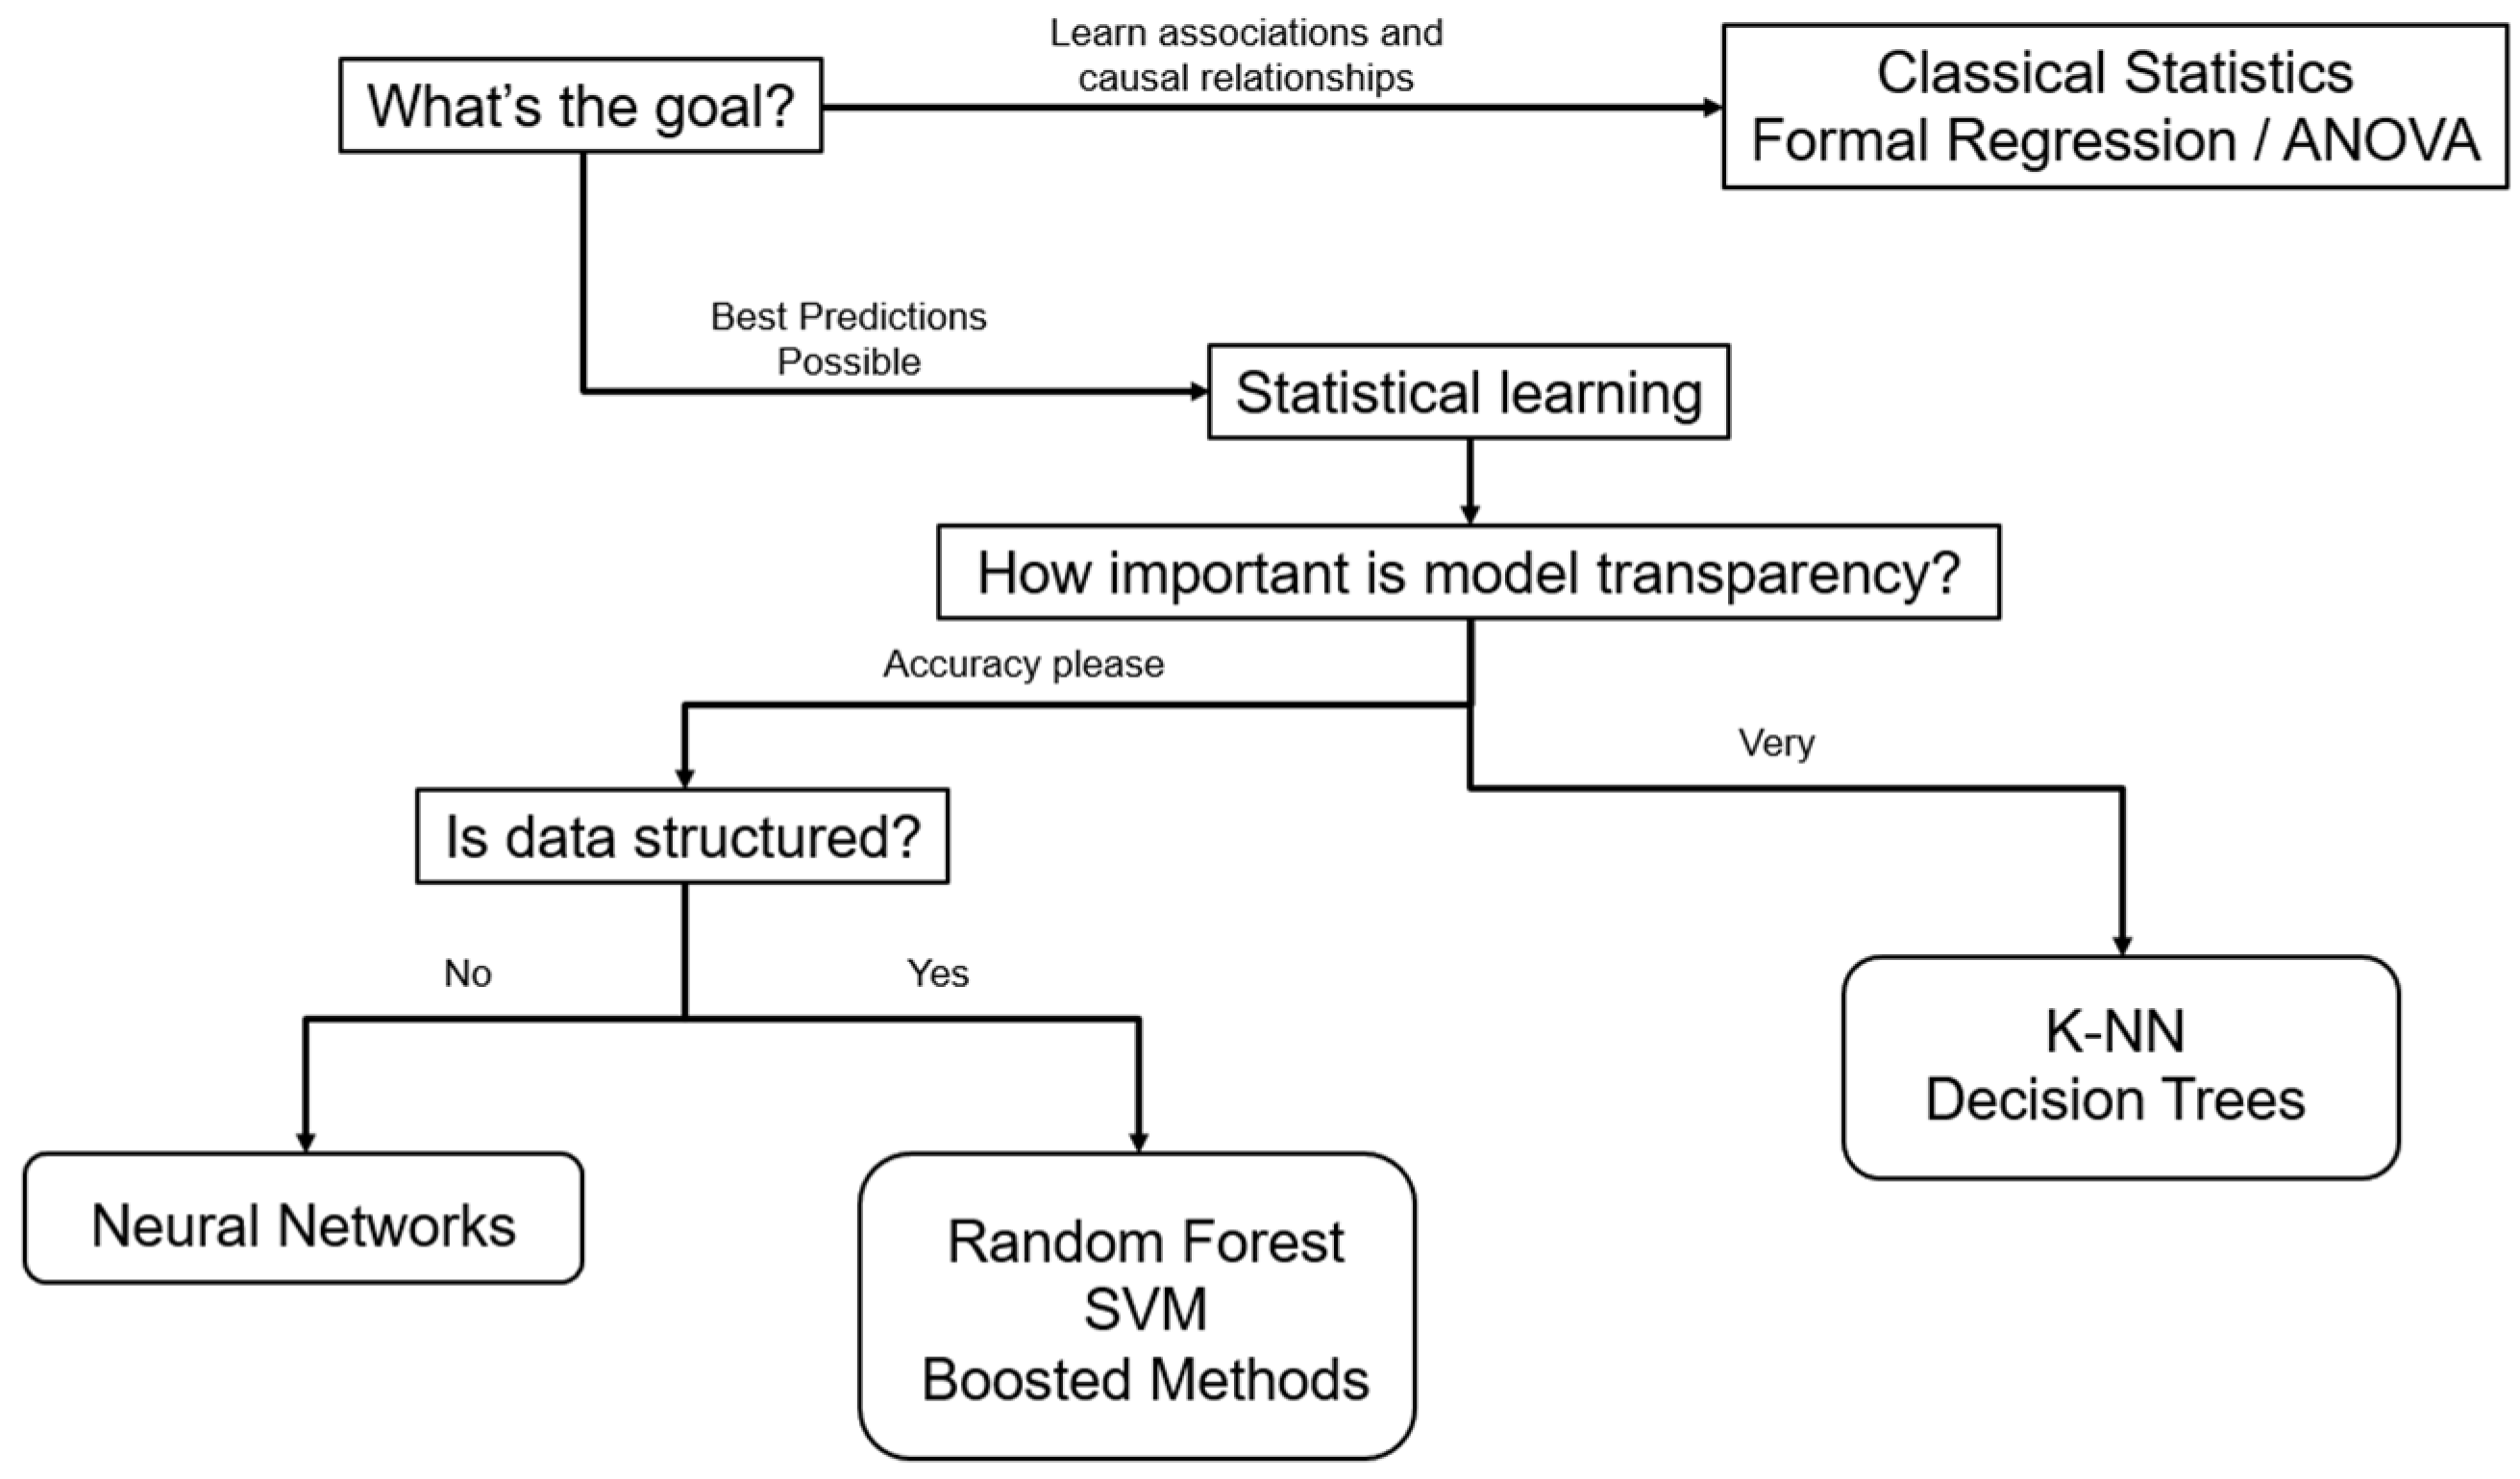

Through techniques from the fields of machine learning (ML) and deep learning (DL) (

Figure 1), AI systems can detect complex, nonlinear relationships between data and outcomes. This is particularly useful in the presence of nonlinear relationships in spinal deformity data, such as how patient satisfaction relates to health-related quality of life (HRQoL) and complications [

Figure 3 illustrates the authors’ preferred algorithm for choosing the proper off-the-shelf ML methods based on study data and purposes.